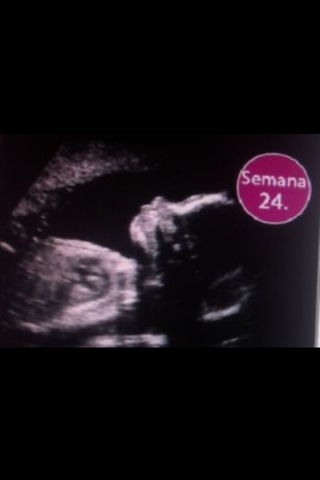

El sistema digestivo, circulatorio y respiratorio ya están maduros

Se deposita el pigmento del bebe que colorea su piel

Los oídos, olfato y pupilas gustativas ,nervios del tacto ya están maduros